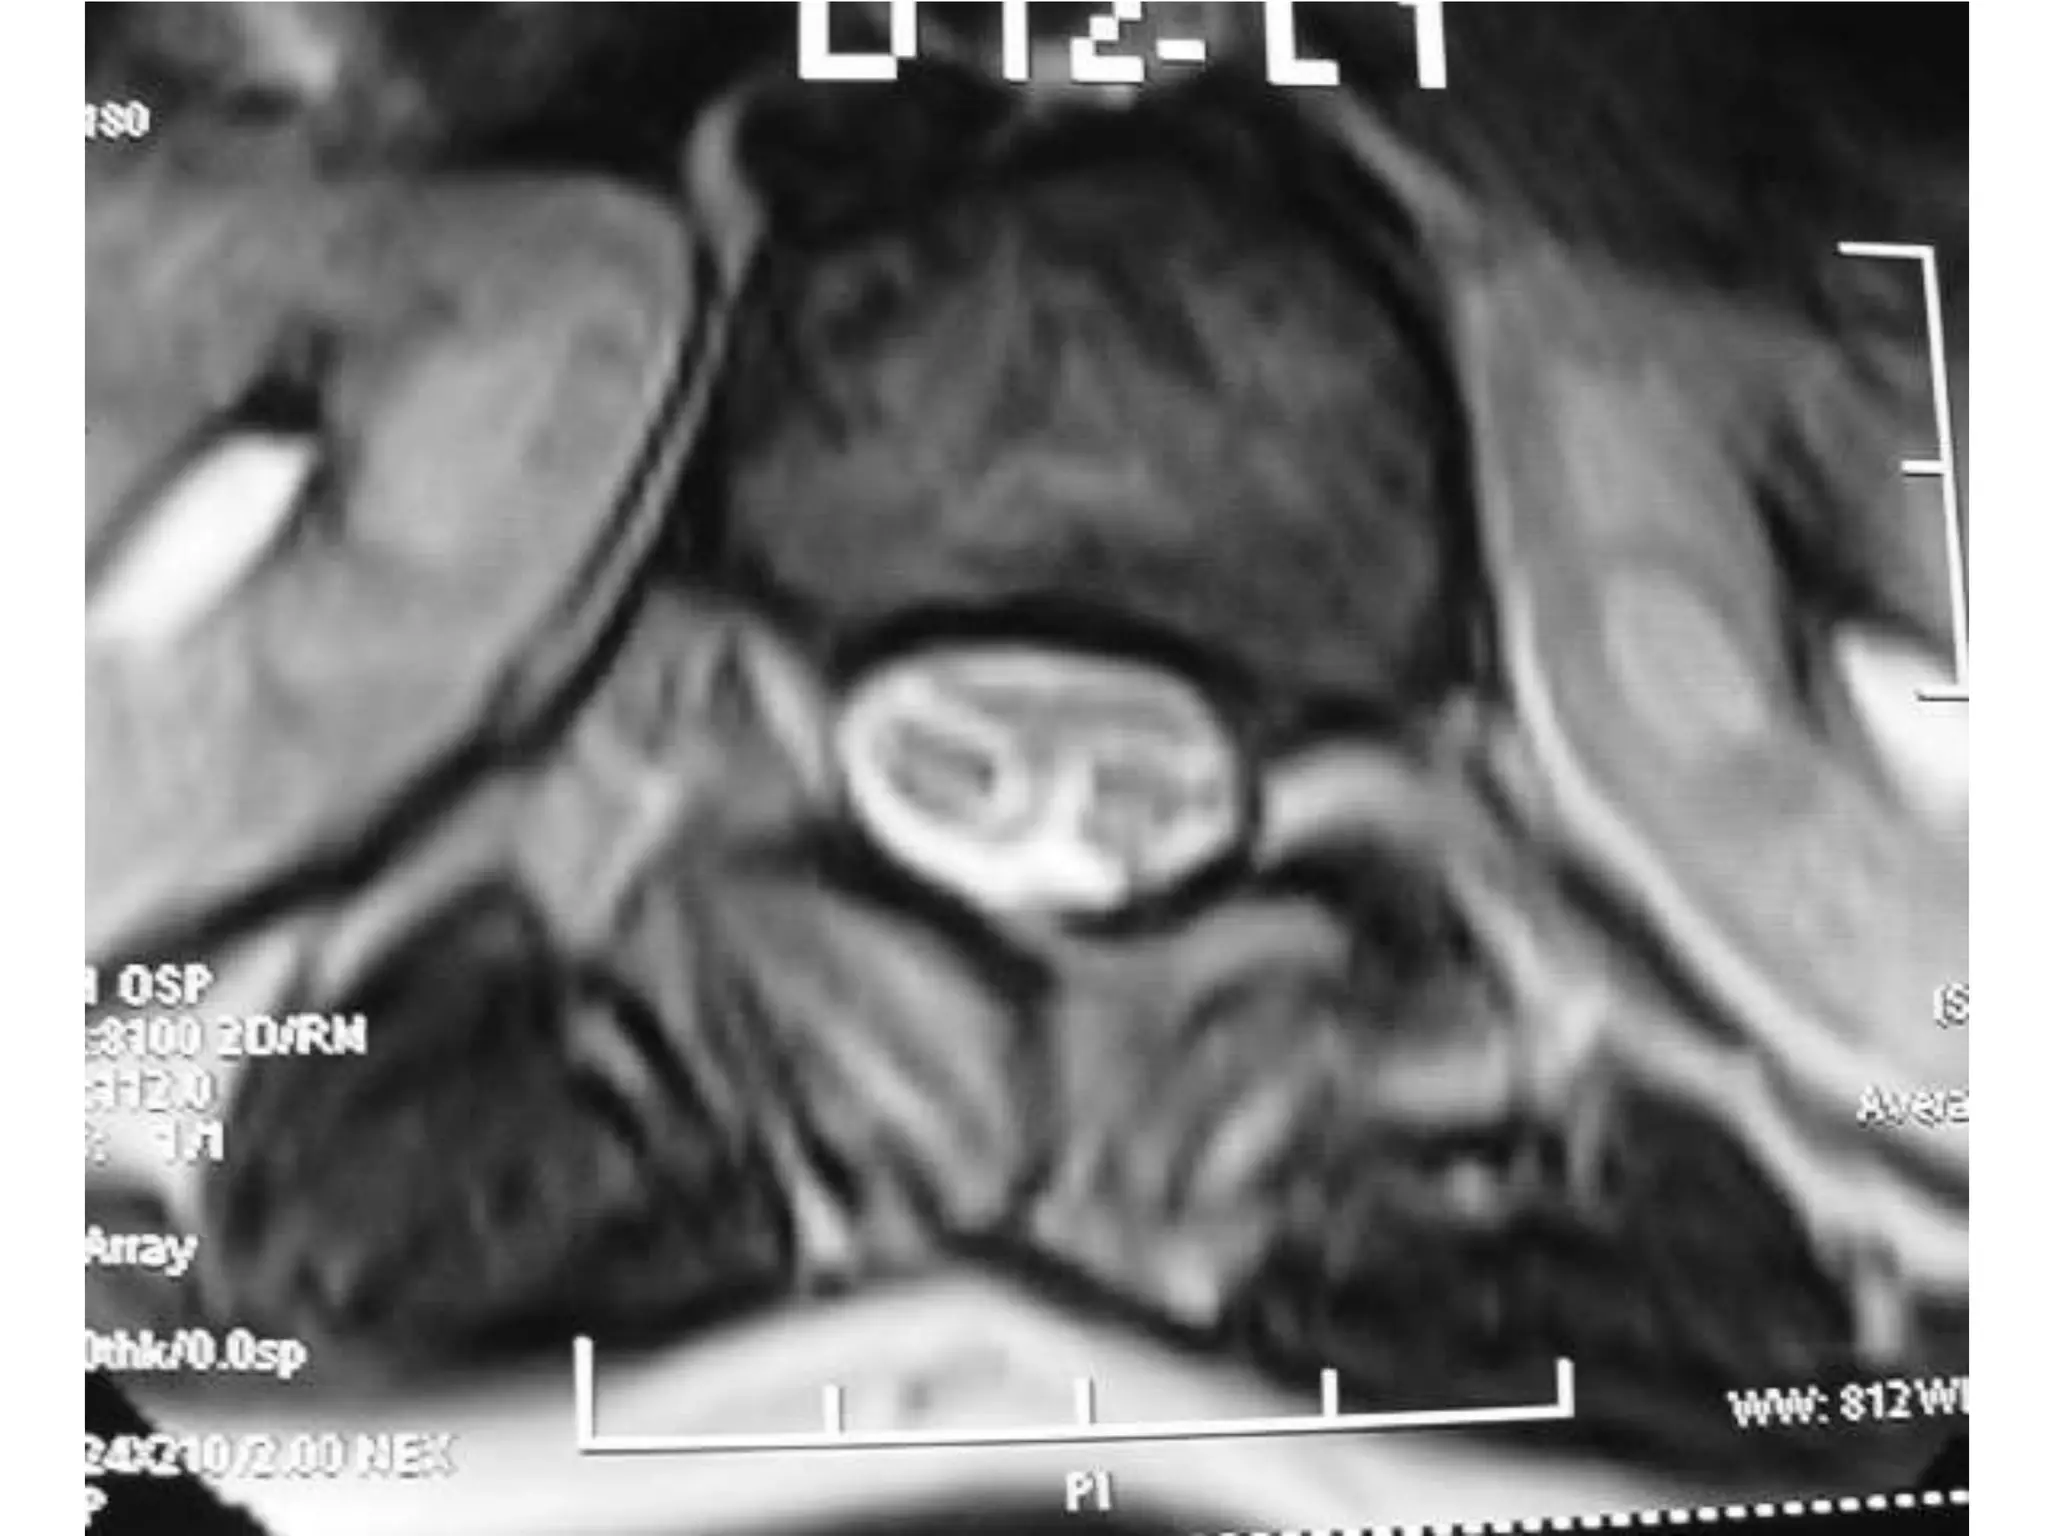

Disc at D12 – L1